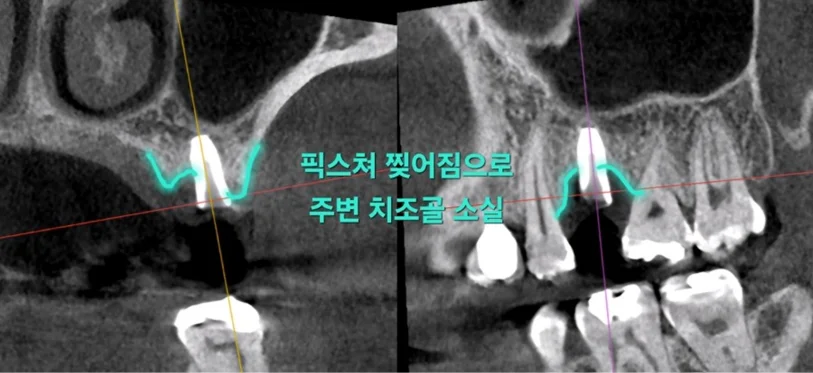

CT 촬영 결과, 파절된 픽스쳐 주위로 치조골 소실도 확인되어 상악동 거상술이 함께 필요한 상황이었습니다.

▲ CT 이미지: 치조골 소실 및 상악동 확인